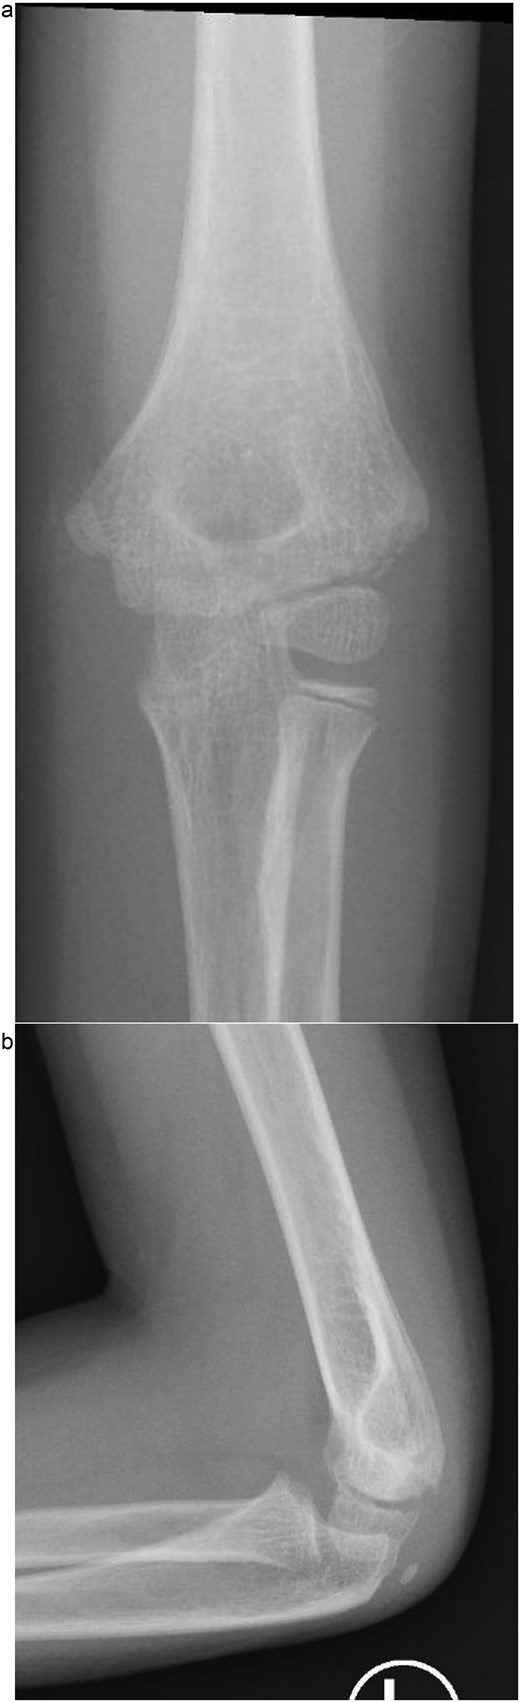

Under procedural sedation, closed reduction of the elbow dislocation was performed, restoring joint alignment and stability. However, post-reduction imaging showed persistent displacement of the lateral condyle fragment (Fig. 2a). The patient was subsequently taken to the operating room, where closed reduction of the condylar fracture was carried out under general anesthesia. As post-reduction displacement was less than 2–4 mm with intact articular cartilage, fixation was performed using two smooth Kirschner wires under fluoroscopic guidance. An arthrogram confirmed joint congruity and cartilage integrity (Fig. 3a). A long-arm posterior slab was applied with the elbow in <90° of flexion to minimize the risk of compartment syndrome (Fig. 4a).

(a) Immediate post-reduction anteroposterior radiograph showing restored joint alignment with persistent lateral condyle displacement. (b) Lateral view confirming maintained reduction of the ulnohumeral joint and residual separation of the lateral condyle fragment.